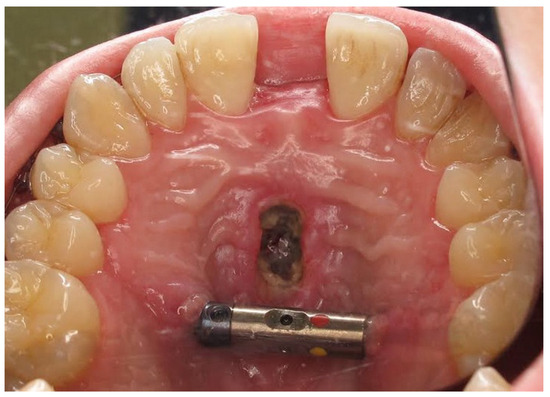

| No possibility of distraction—1 case | Maxillary incisor root resorption—2 cases |

| Palatal mucosal necrosis—2 cases | Bone loss/lack of adhesion in the distraction gap—5 cases |

| Perforation of the maxillary alveolar process caused by the distractor—1 case | Maxillary incisor necrosis—2 cases |

| Asymmetric distraction—5 cases | |